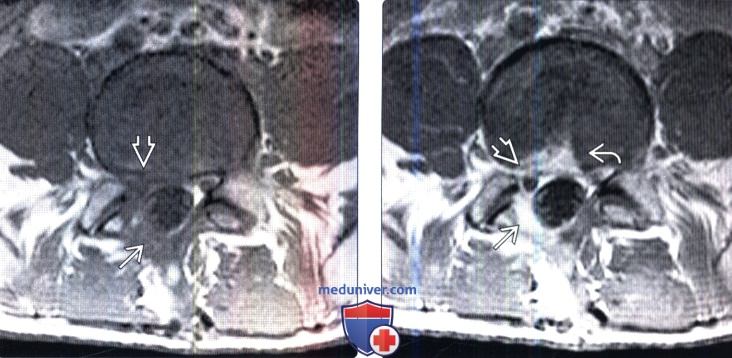

КТ ретроперитонеального фиброза: Изображения и диагностика